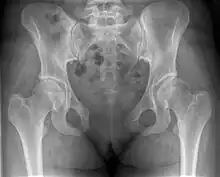

Separation of the symphysis pubis (diastasis)

An X-ray film obtained in the AP view of the pelvic inlet and outlet will show a marked gap between the pubic bones.[3] A normal pelvis will show a gap that is 4–5 mm. However, in pregnancy the hormonal influences cause relaxation of the connecting ligaments and the bones separate up to 9 mm. A gap measuring greater than 10 mm indicates a pathological process.[3]

In addition, a view in the "flamingo stance" can be obtained to demonstrate the instability of the joint. This position consists of the patient standing with weight on one leg and the other bent.[6] A vertical displacement of more than 1 cm is an indicator of symphysis pubis instability.[7] A displacement of more than 2 cm usually indicates involvement of the sacroiliac joints.[3]